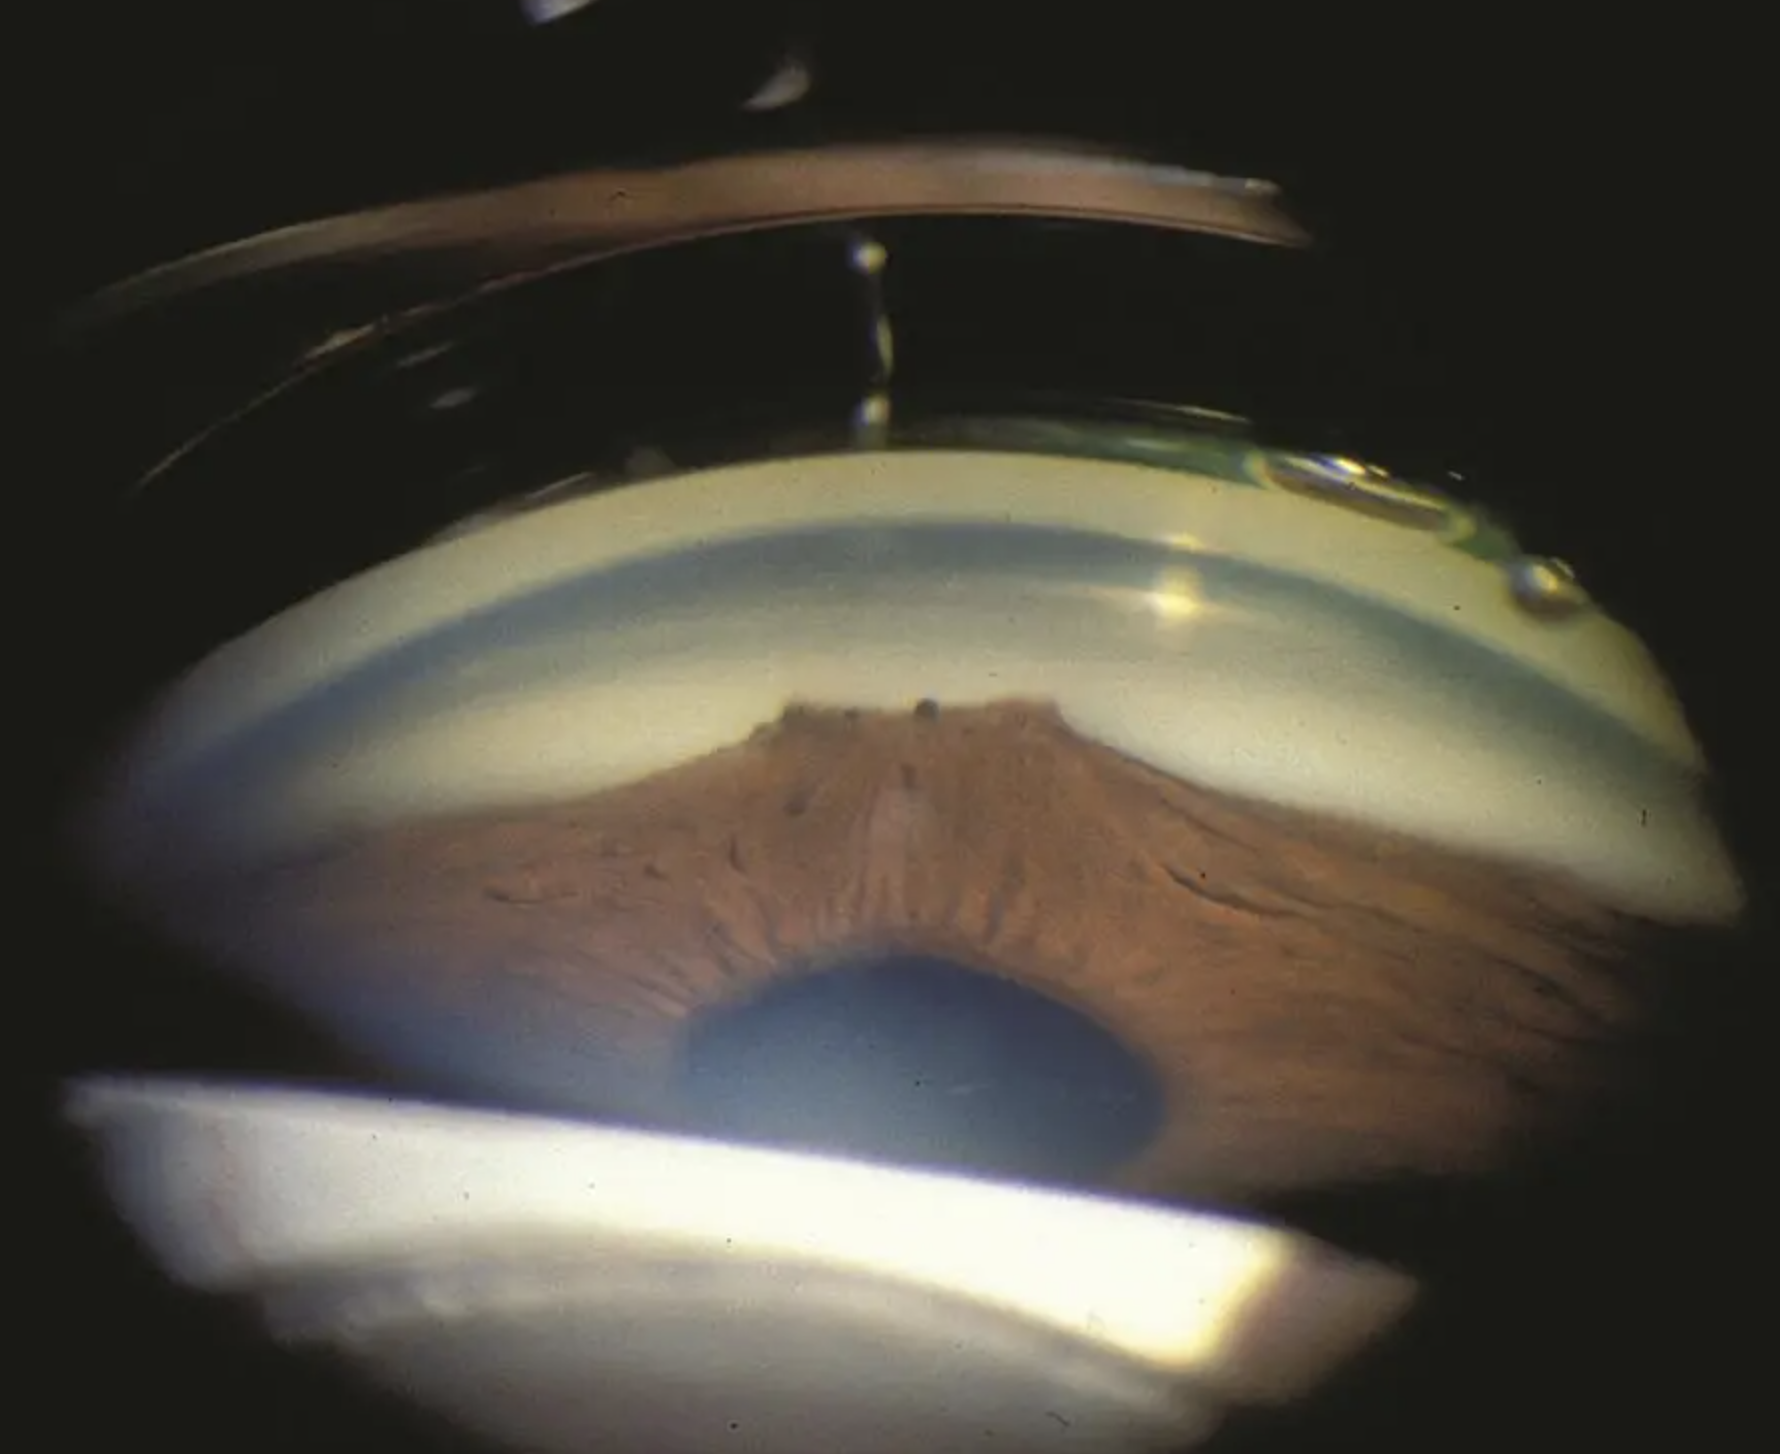

First step: determine if you can see structures. Here’s a mnemonic, from posterior to anterior:

I Can’t See This Sh…tuff.

Iris, Ciliary body, Scleral spur, Trabecular meshwork, Schwalbe’s line

But how do you describe what you are seeing?

There are many ways to describe the angle. The simplest way: open, narrow, closed, hyper-deep.

Another way is to simply describe what you can see, for instance:

Open to ciliary body band 360, light pigmentation

Open to scleral spur 270, to TM superiorly, heavy pigmentation

Open to scleral spur 360, patchy pigmentation, +sampaolesi line

Narrow, scattered PAS, areas of NVA

Angle recession from 3 to 8 o’clock